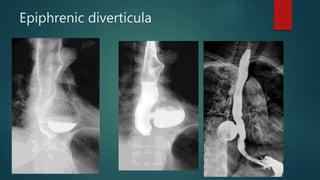

Epiphrenic diverticula

• #121 Large wide necked diverticulum arising several centrimetres proximal to the GOJ. The diverticulum contains a progressively filling air fluid-level following barium consumption. Normal calibre oesophagus - no stricture. No hiatus hernia.